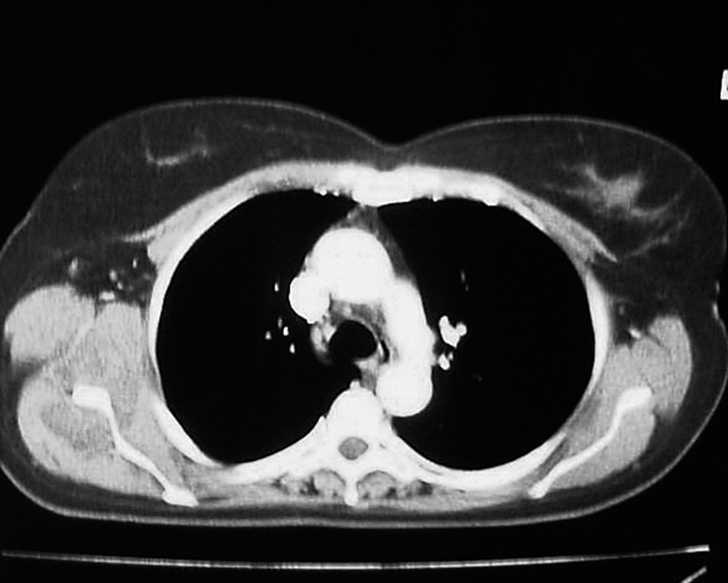

De las cuatro restantes tumoraciones infraescapulares estudiadas, reflejadas en la tabla 1, dos fueron liposarcomas, una fue un lipoma intramuscular y, la última, un hematoma asociado a rotura muscular. En todas ellas se planteó el ED como diagnóstico diferencial. En el caso 6 se halló una tumoración subescapular de unos 10 cm de diámetro en el contexto del estudio de una masa en el muslo derecho, cuya PAAF previa fue indeterminada, y que finalmente correspondió a un liposarcoma multicéntrico metastásico (fig. 7). El caso 7 correspondió a una masa escapular como diseminación de un liposarcoma mixoide en muslo (fig. 8). En el caso 8 se planteó el diagnóstico de elastofibroma por sus características clínicas, descartándolo tras una RMN y llegando al diagnóstico definitivo de lipoma intramuscular tras la resección (fig. 9). El caso 9 corresponde a un varón joven que presentaba una tumoración blanda y elástica en región subescapular de unos 5 cm de diámetro, de tres semanas de evolución y que molestaba con la tos. El estudio por ecografía fue suficiente para llegar al diagnóstico de ruptura muscular y hematoma secundario.

Figura 7. Masa subescapular cuyo diagnóstico final fue de liposarcoma multicéntrico metastásico.